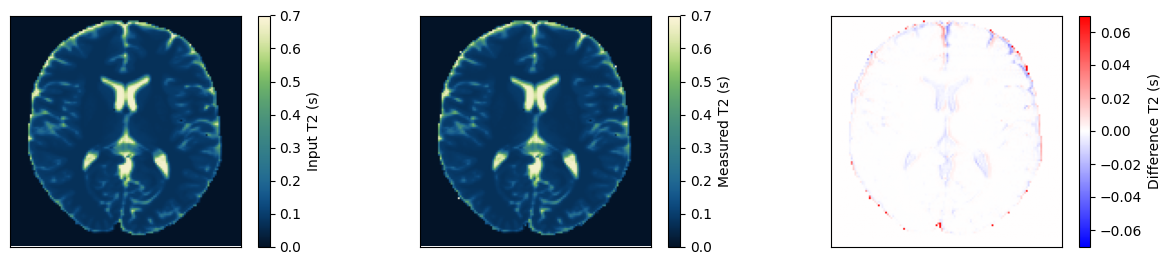

Estimate the T2 maps#

We use a dictionary matching approach to estimate the T2 maps. Afterward, we compare them to the input and ensure they match.

dictionary = DictionaryMatchOp(MonoExponentialDecay(decay_time=idata.header.te), index_of_scaling_parameter=0)

dictionary.append(torch.tensor(1.0), torch.linspace(0.01, 0.8, 1000)[None, :])

m0_match, t2_match = dictionary(idata.data[:, 0, 0])

t2_input = np.roll(rearrange(phantom.T2.numpy().squeeze()[::-1, ::-1], 'x y -> y x'), shift=(1, 1), axis=(0, 1))

obj_mask = np.zeros_like(t2_input)

obj_mask[t2_input > 0] = 1

t2_measured = t2_match.numpy().squeeze() * obj_mask

fig, ax = plt.subplots(1, 3, figsize=(15, 3))

for cax in ax:

cax.set_xticks([])

cax.set_yticks([])

im = ax[0].imshow(t2_input, vmin=0, vmax=0.7, cmap=Colormap('navia').to_mpl())

fig.colorbar(im, ax=ax[0], label='Input T2 (s)')

im = ax[1].imshow(t2_measured, vmin=0, vmax=0.7, cmap=Colormap('navia').to_mpl())

fig.colorbar(im, ax=ax[1], label='Measured T2 (s)')

im = ax[2].imshow(t2_measured - t2_input, vmin=-0.07, vmax=0.07, cmap='bwr')

fig.colorbar(im, ax=ax[2], label='Difference T2 (s)')

relative_error = np.sum(np.abs(t2_input - t2_measured)) / np.sum(np.abs(t2_input))

print(f'Relative error {relative_error}')

assert relative_error < 0.02

Relative error 0.011909615248441696

_images/8df5db2cca9a92321b100cc81b514a24d15b6748c661416f504509ecf0c55f86.png